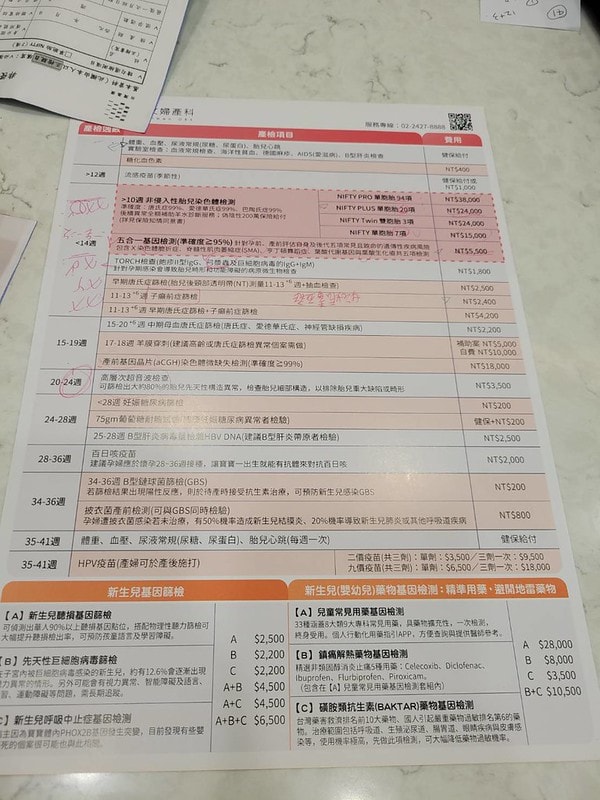

關於高齡產婦該做什麼檢查?

我做了NIPT+五合一+子癲前症總共大概三樣檢查

花了三萬二左右

但如果你們想要更精準的檢查

可以直接做羊膜穿刺+羊水晶片

羊穿過35歲大概有補助5000

所以差不多抓5000+18000~28000左右的價格

不過每間診所不一樣啦

北部跟南部應該也有差異

14周前一定要先做NIPT

16~18周則是比較適合做羊膜穿刺

費用大概是5500左右

非侵入性胎兒染色體檢測

我的診所有7項、20項、94項

費用從15000~38000都有

簡單來說做越多費用就越高啦

看你們自己預算上的考量

但基本上是建議一定要做的

因為高齡產婦生出唐氏症小孩的機率比較高

子癲前症也是高齡產婦可以做的檢查之一,發生率約5%

所以我就是做了以上說的NIPT+五合一+子癲前症這三樣檢查